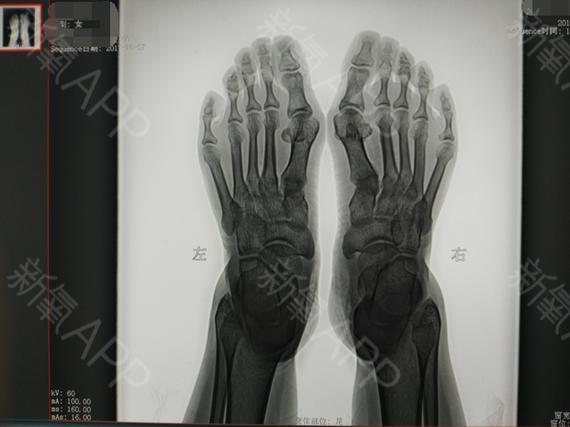

天生的大脚骨,x光片上能够清晰的看到大拇指外翻特别

脚骨图片x光片

轻度大脚骨图片